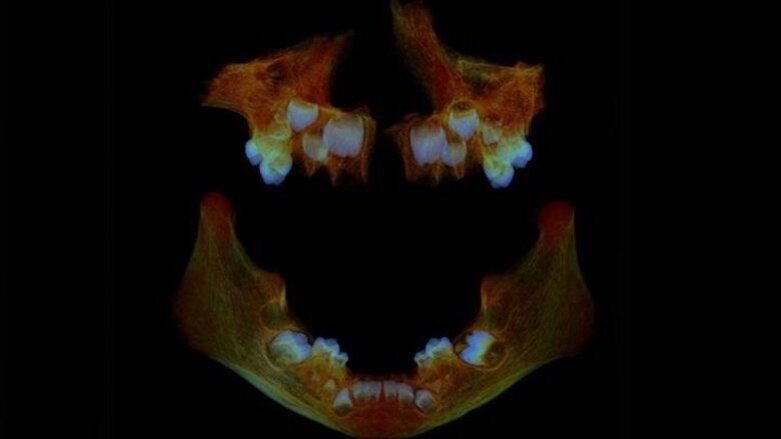

By analysing dentine from the primary teeth of the skeletons, the research team was able to create a picture of the development of these children from the third trimester of pregnancy onwards. They were also able to look at children of different ages to see if those who survived the first 1,000 days from conception, a period during which factors such as height are determined, had different biomarkers for stress than those who died during this period.

“We find that when bone and teeth form at the same time, bone doesn’t record high nitrogen values that occur during stress. Our hypothesis is that bone isn’t growing but teeth are. So archaeology can’t rely on the evidence from bones alone because bone is not forming and recording during high stress and we can’t be sure, for example, of the age of a skeleton. Teeth are more reliable as they continue to grow even when a child is starving,” she continued.